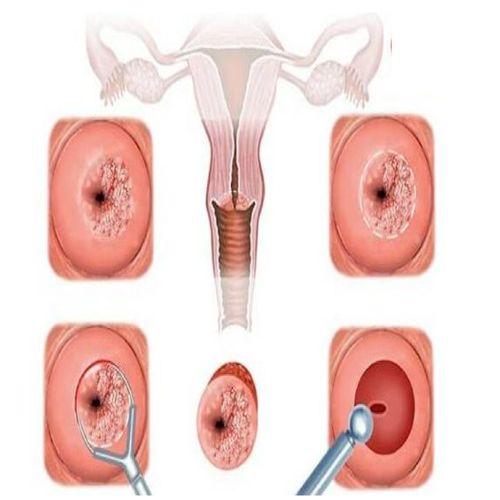

Viêm cổ tử cung là tình trạng viêm nhiễm, phù nề và sưng mủ lở loét tại vùng cổ tử cung do tác động trực tiếp từ vi khuẩn gây hại, nấm men, ký sinh trùng hay virus. Bệnh có thể gây đau đớn nhiều cho chị em, đặc biệt ở vùng hạ vị, rối loạn chu kỳ kinh nguyệt và chức năng vốn có của cổ tử cung.

Ngoài ra, cổ tử cung, dài khoảng 5cm, nằm ở vị trí tiếp giáp của buồng tử cung và khu vực âm đạo. Vì vậy mỗi khi bị viêm nhiễm, chúng có thể lây lan ở cấp độ rộng và gây nên nhiều biến chứng xấu. Bệnh được chia thành 2 cấp độ:

Thăm khám lâm sàng: Bác sĩ sử dụng mỏ vịt (dụng cụ khám âm đạo chuyên dụng) để đưa vào vùng kín và kiểm tra âm đạo, cổ tử cung, buồng tử cung. Hầu hết sẽ quan sát thấy được những dịch trắng bị ứ đọng tại thành tử cung, có thể màu vàng hoặc xanh. Ngoài ra, niêm mạc tử cung sẽ bị lộ ra ngoài tạo thành các lộ tuyến, gây phù nề niêm mạc và dễ bị chảy máu.